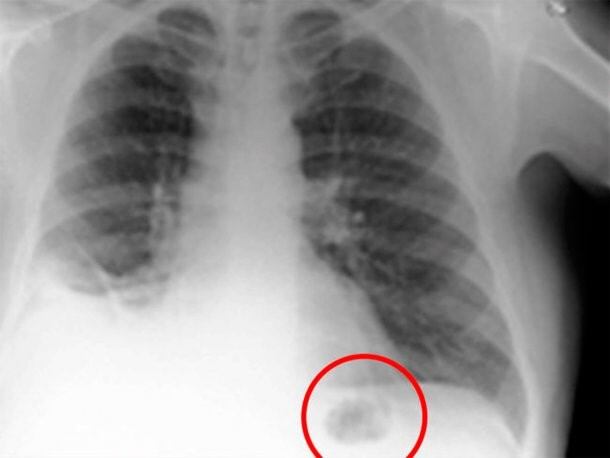

Un hombre de Preston, Inglaterra, pensaba que tenía cáncer de pulmón tras realizarse una radiografía y encontrar una mancha. Es que los médicos vieron una sombra negra y anticiparon lo peor.

Sin embargo, luego los estudios médicos arrojaron que se trataba de ¡una pieza de Playmobil!

Sin embargo, las pruebas realizadas en el Royal Preston Hospital demostraron que era un pequeño cono de tráfico de Playmobil que se había tragado cuando tenía 7 años.